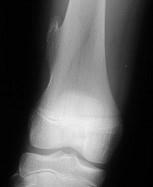

男,13岁,运动后膝痛,请结合影像图像,选择最可能的诊断()A.正常影像B.动脉瘤样骨囊肿C.骨软骨瘤D.成骨细胞瘤E.骨样骨瘤

问题 男,13岁,运动后膝痛,请结合影像图像,选择最可能的诊断()

选项 A.正常影像 B.动脉瘤样骨囊肿 C.骨软骨瘤 D.成骨细胞瘤 E.骨样骨瘤

答案 C